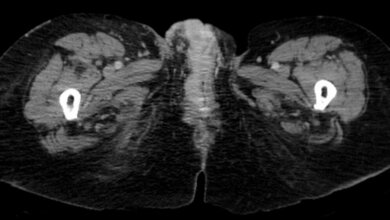

Lymphödeme, bei denen sich die Lymphe im Gewebe staut statt abzufließen, sind oft Behandlungsfolgen von Krebserkrankungen. Die Operation oder Bestrahlung haben dann zwar den Tumor beseitigt, gleichzeitig aber auch das empfindliche Lymphsystem gestört. „Diese Störungen sind für die Betroffenen sehr schwerwiegend und mit hohem Leidensdruck verbunden“, beschreibt Prof. Stefan Langer, Leiter des Bereichs Plastische und Wiederherstellende Chirurgie am Universitätsklinikum Leipzig. Das schwere und geschwollene Gewebe ist nicht nur optisch unschön, es entsteht auch ein sehr unangenehmes, schmerzhaftes Druckgefühl. Zudem passen die Patientinnen und Patienten nicht in ihre Kleidung. Bis vor wenigen Jahren standen hier zur Behandlung nur Maßnahmen wie Lymphdrainage oder das Tragen von Kompressionsstrümpfen zur Verfügung. „Für die Patienten sind diese ständigen Entstauungstherapien langfristig sehr belastend, allerdings eben auch die bisher einzige Maßnahme“, so Langer. „Eine echte Heilungschance gab es nicht.“

Ein neuer Ansatz schafft hier jetzt Abhilfe: Gesunde Lymphknoten werden mikrochirurgisch transplantiert, zerstörtes Gewebe rekonstruiert und die Funktion wieder hergestellt. „Wir können endlich etwas anbieten, was tatsächlich wirksam das Problem lösen kann“, ist Prof. Langer begeistert. Seit mehr als einem Jahr setzt er dazu gesunde Lymphknoten anstelle der beschädigten ein. Bei dieser Lymphknoten-Transplantation werden gesunde Lymphnoten an einer Stelle entnommen, wo deren Fehlen keine Funktionen beeinträchtigt. „Wir entnehmen dazu mit Unterstützung unserer Viszeralchirurgen winziges Fettgewebe aus dem Bauchraum“, erklärt Langer. In einer mehrstündigen Operation werden diese dann unter einem speziellen OP-Mikroskop verbliebenen, weniger als 1 Millimeter dicken Lymphgefäßen verbunden und übernehmen dann die Aufgabe des fehlenden Lymphknotens.